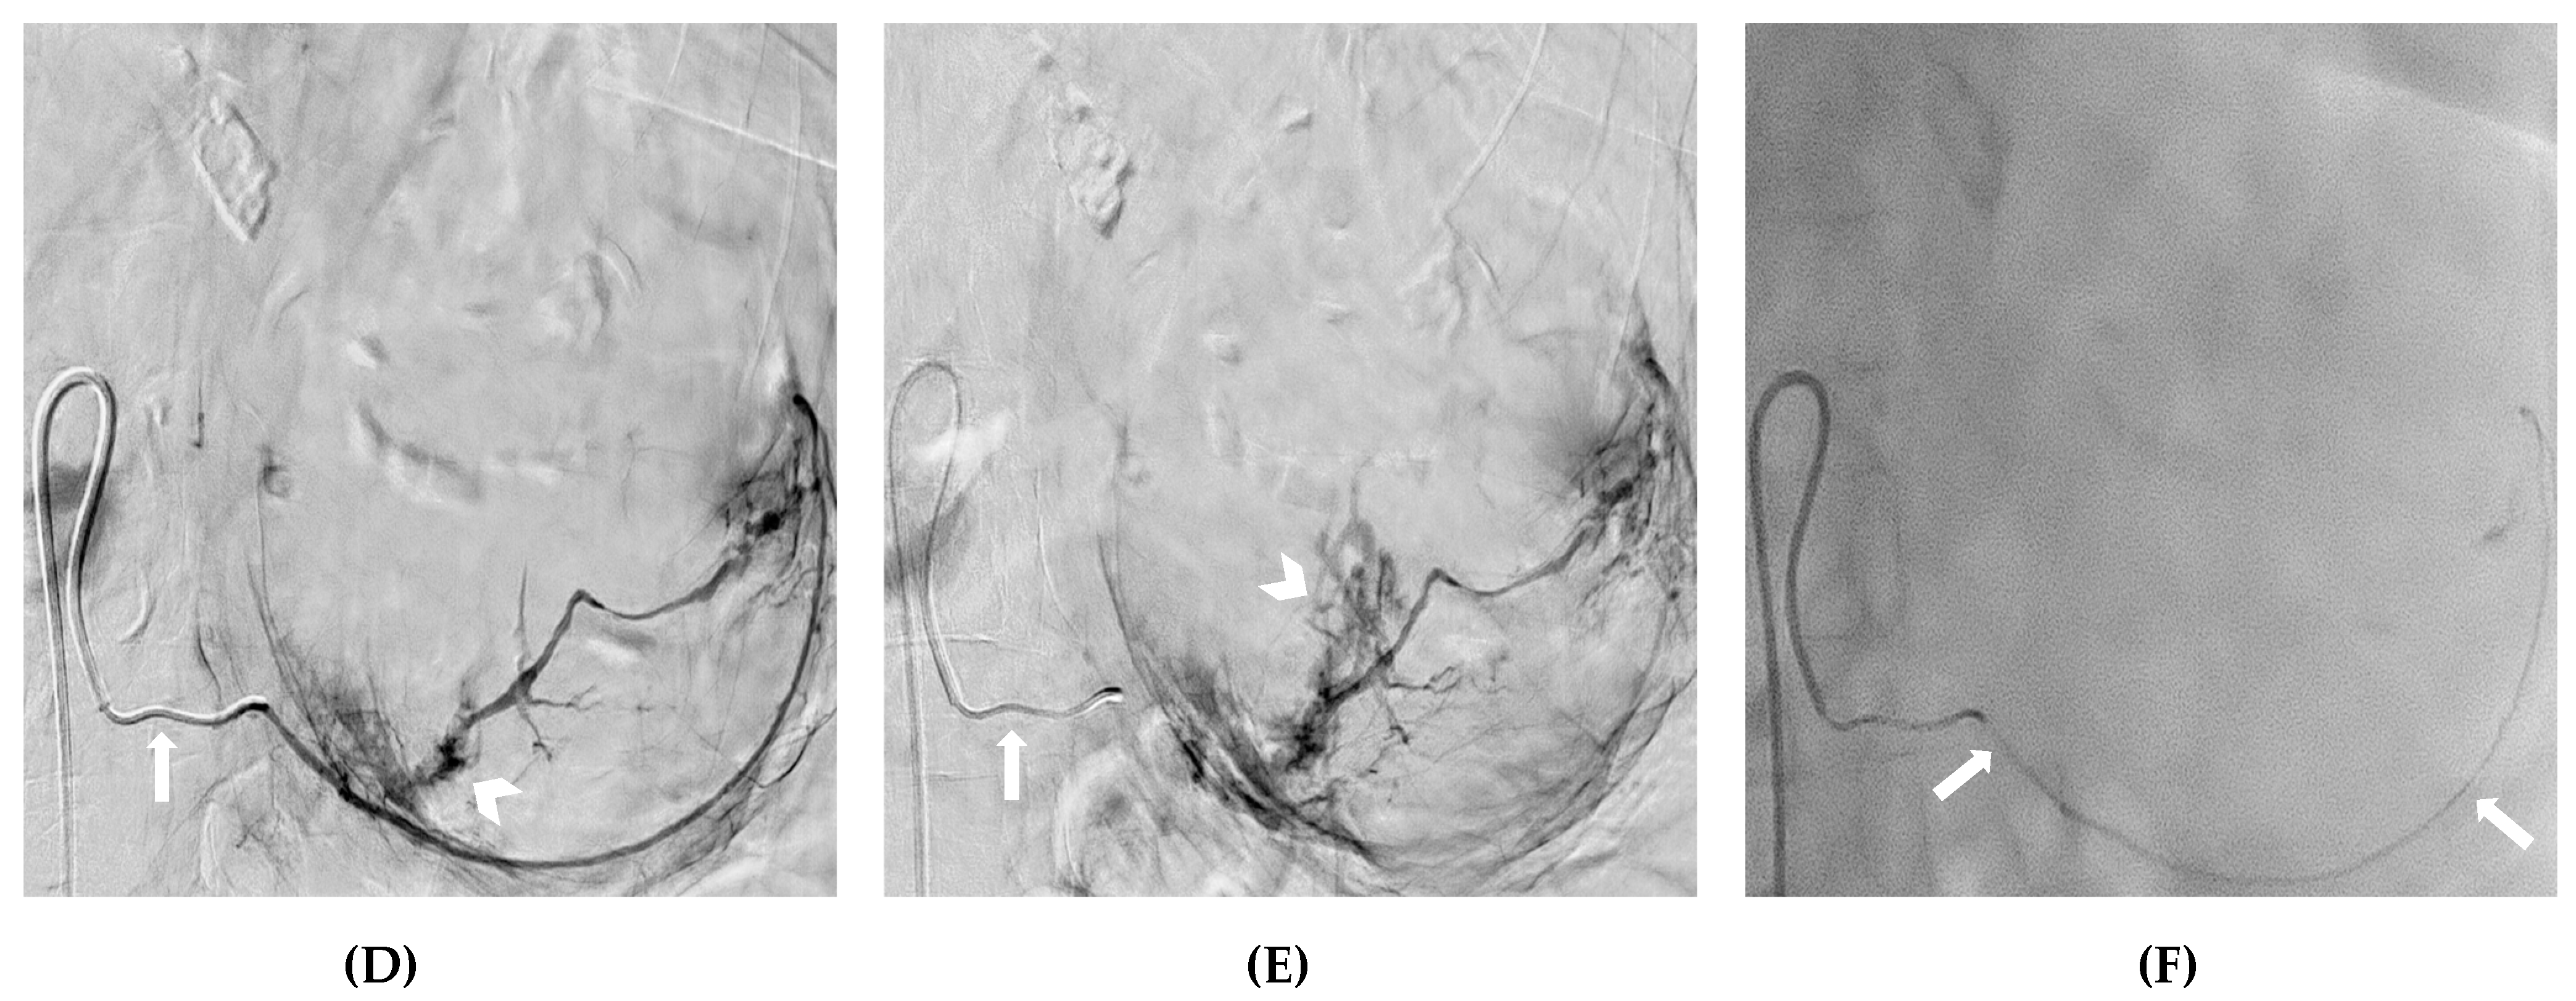

- Atzori, G.; Diaz, R.; Gipponi, M.; Cornacchia, C.; Murelli, F.; Depaoli, F.; Sparavigna, M.; Barbero, V.; Petrocelli, F.; Pitto, F.; et al. A Case of Life-Threatening Bleeding Due to a Locally Advanced Breast Carcinoma Successfully Treated with Transcatheter Arterial Embolization. Curr. Oncol. 2023, 30, 2187–2193. [Google Scholar] [CrossRef]